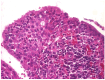

Background: This study presents a comprehensive analysis of cholesteatoma of the middle ear, focusing on its clinical presentation, diagnostic imaging, and treatment outcomes. Cholesteatomas are defined by the keratinized squamous epithelium within the middle ear, leading to significant bone erosion, often affecting the ossicular chain and surrounding structures. Methods: The study explores various mechanisms involved in cholesteatoma progression, including enzymatic lysis, inflammatory responses, and neurotrophic disturbances. The study conducted a retrospective clinical and statistical review of 580 patients over a 20-year period (2003-2023), highlighting the role of advanced imaging, including computed tomography (CT) and diffusion-weighted magnetic resonance imaging (DWI), in preoperative planning and postoperative follow-up. Results: Findings revealed that early detection and intervention are crucial in preventing severe complications such as intracranial infection and hearing loss. Surgical treatment primarily involved tympanoplasty and mastoidectomy, with a recurrence rate of 1.55% within two years. The study underscores the importance of integrating imaging advancements into clinical decision-making to enhance patient outcomes and suggests further investigation into molecular mechanisms underlying cholesteatoma progression and recurrence. Histopathological and microbiological analysis was performed to identify pathological patterns and microbial agents. Conclusions: The study highlights the importance of early diagnosis and intervention to prevent complications such as intracranial infections and permanent hearing loss, while also emphasizing the role of advanced imaging techniques in the management and long-term monitoring of cholesteatoma patients.